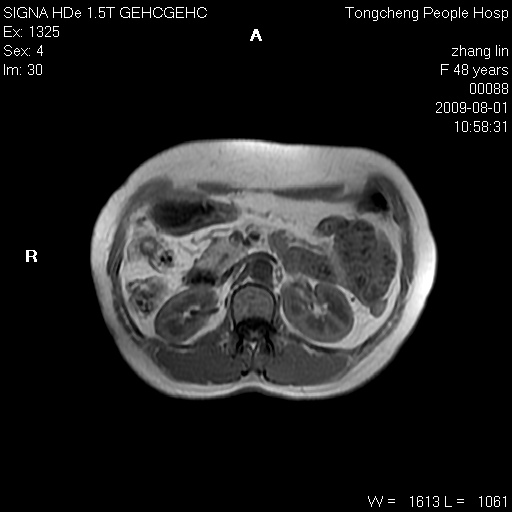

女,48岁。健康体检,彩超发现右肾占位性病变。平素健康。

临床诊断:右肾占位性病变,性质待定(囊肿?肿瘤?)。

上中腹部mr平扫+增强扫描,图像如下:

右肾上极见一类圆形病灶,t1wi呈等信号t2wi呈等高混杂信号,三期增强无强化,边界清---考虑囊肿出血。

同反相位均表现为等信号,病变无强化,考虑含蛋白的囊肿可能,弥散加权相或许有些帮助,

慢性胆囊炎